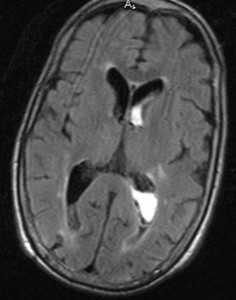

МРТ головного мозга. Аксиальная МРТ типа FLAIR. Аневризма и САК, внутрижелудочковое кровоизлияние.

МРТ головного мозга. Аксиальная Т2-взвешенная МРТ типа FLAIR. Внутрижелудочковое кровоизлияние.